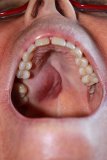

DEVELOPMENT AND FUNCTION OF THE MOUTH AND PHARYNX SUBMUCOSA: The mouth is the opening of the alimentary canal and the place where the digestion (secretory quality) and absorption (absorptive quality) of food starts. The tongue is an accessory digestive organ that aids in chewing and swallowing. Through chewing, food is broken into small pieces. Saliva produced in the salivary glands moistens the food bolus to make swallowing easier. The salivary glands are located in several parts of the mouth. The largest salivary glands are the parotid glands in front of the ears, the sublingual glands underneath the tongue, and the submandibular glands beneath the lower jaw. The pharynx connects the mouth and nasal cavities with the trachea and the larynx. The nasopharynx, located in the back of the nose, extends to the upper surface of the palate which forms the roof of the mouth; the oropharynx is at the very back of the mouth. On both sides of the pharynx lie the tonsils. Branching off the pharynx is the esophagus that carries food from the mouth to the stomach. The submucosa of the mouth and pharynx (including the lips, gums, palate, tongue, salivary glands, tonsils, and throat) consists of intestinal cylinder epithelium, originates from the endoderm and is therefore controlled from the brainstem.

DEVELOPMENT AND FUNCTION OF THE MOUTH AND PHARYNX SURFACE MUCOSA: The submucosa of the mouth and pharynx is covered with a cell layer composed of squamous epithelium, which derives from the ectoderm and is therefore controlled from the cerebral cortex. NOTE: The tonsils do not have an ectodermal surface mucosa.